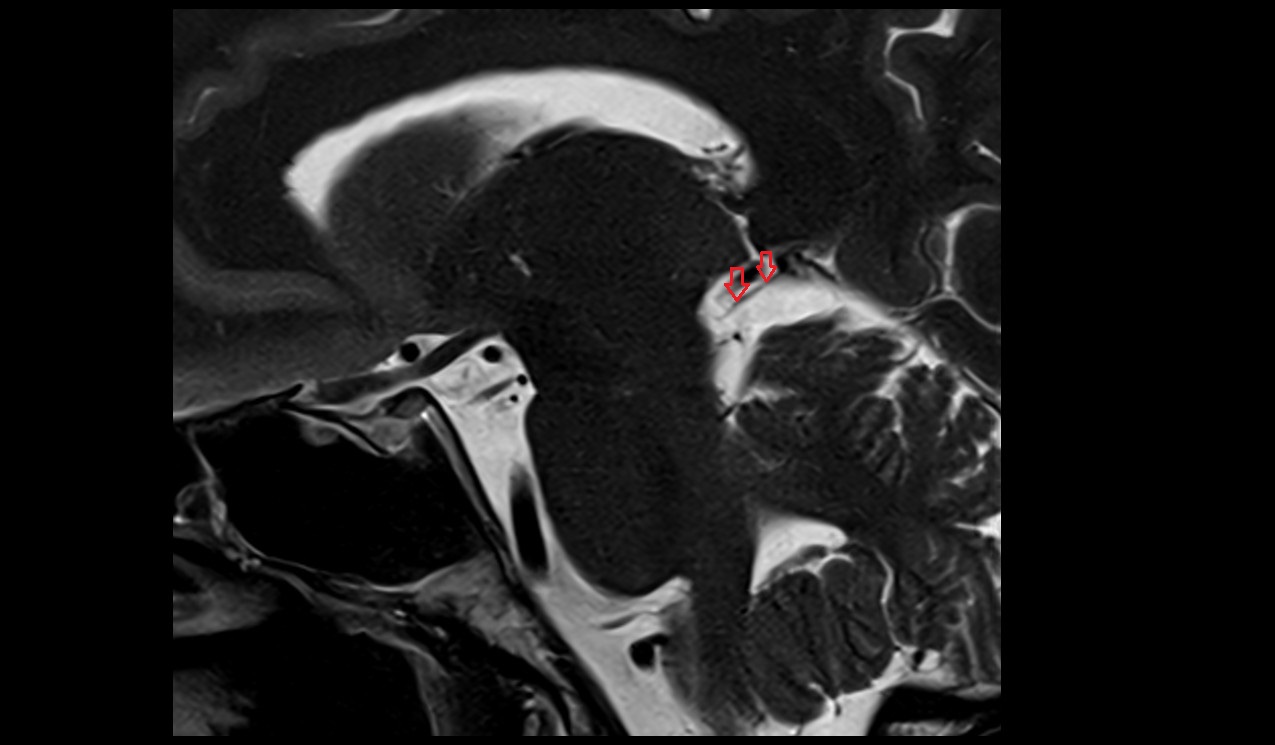

- Median aperture of fourth ventricle (foramen of Magendie)